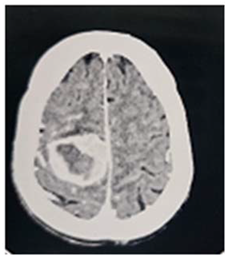

This is 16 years male, off school, experiences history of febrile illness and headache for long duration, presented to neurosurgery emergency unit with convulsions and deterioration level of consciousness this was 4 months before his presentation.

On examination: he was unwell, severe loss of weight, dry skin with multiple café aulate spots all over his body; there was bilateral eye globe proptosis.

Patient was admitted to ER and resuscitation was done

Preprints 114904 i002

Operation: After clear counseling to the family, subsequently Left fronto –tempro-parietal craniotomy was done, operative findings: very thin bone with multiple eaten parts, the dura was very thin and adherent to the over lining bone, the tumor itself was multi in components, mucus like material and solid parts and cystic part which contained yellow fluid

In closing the dura, graft from the temporalis fascia was taken and closed in water tide.

Patient was recovered from anesthesia well, taken to the ICU on nasal oxygen

In the first post operative day, the patient showed dramatic improvements in his level of conscious, free of headache. Few weeks post operative; patient came to the clinic walking and looks happy.

Histopathology

Pilocystic astrocytoma